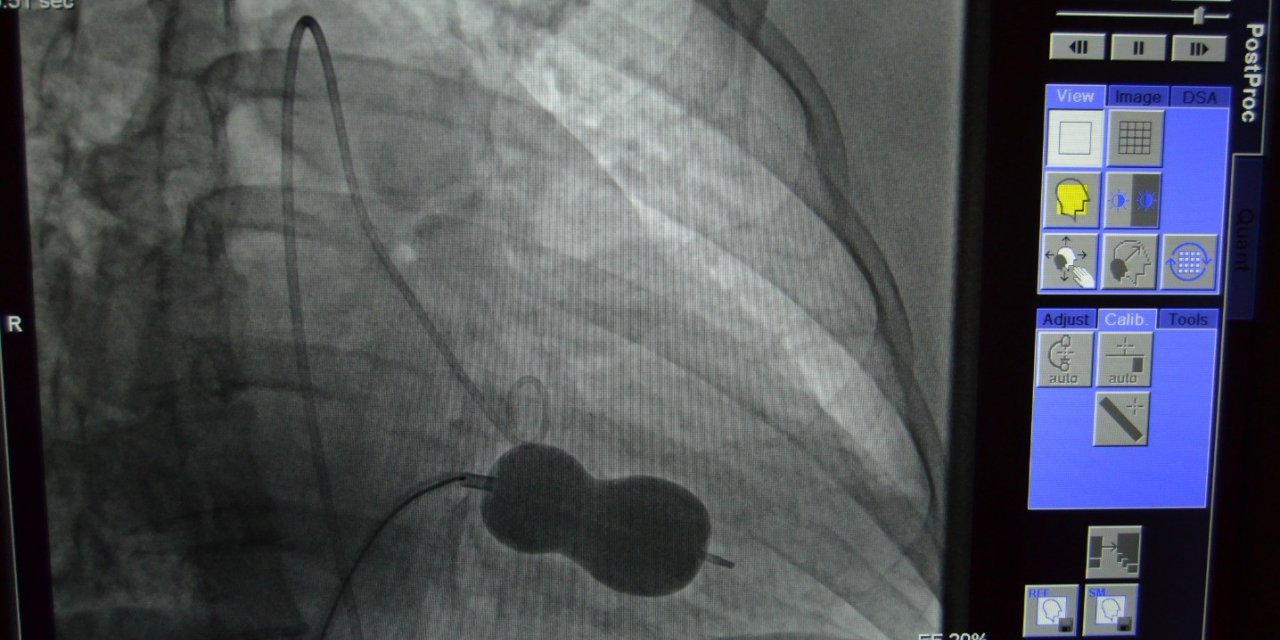

Kalp hastalıklarının teşhisinde altın standart: “Kardiyak MR”